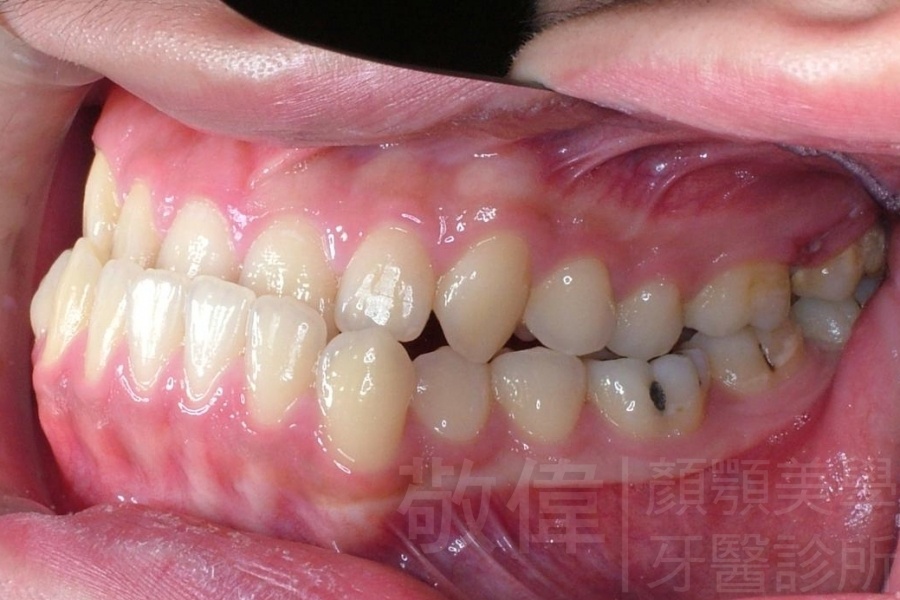

齒顏矯正/戽斗臉型 變身 大帥哥

矯正前-右   矯正前-正   矯正前-左

矯正前-上   矯正前-下

<個案說明>

戽斗(學名第三級咬合 class III)矯正之後,戽斗的樣子就比較沒有了。最主要的改變是在牙齒的咬合。從側面比較,治療前、治療後的臉型 可更明顯看出來 戽斗的感覺 減少了很多。